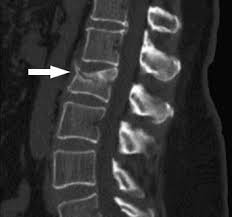

And so: Abdomen/chest CTs can be analyzed automatically for fx risk to identify preventive tx candidates. As 20% of hip fx patients die within a year, this technology is potentially lifesaving, and we plan to implement it at Clalit in 2020. Kudos Noa Dagan & Noam Barda! 4/4pic.twitter.com/Y9mFI47Y6B

CT data of ~50K patients were analyzed by computer vision to produce 3 bone imaging biomarkers: 1) vertebral fractures; 2) simulated T-score; and 3) lumbar trabecular density. These were combined with age and sex (available in CT metadata) to create a CT fracture predictor. 2/4pic.twitter.com/g4CMTiXGhC

We show that CT-driven predictor predicts 5-Y fractures as good as the FRAX score, underutilized in practice as it requires time & awareness to records 18 variables. When FRAX data is available, addition of CT-bone imaging biomarkers significantly improves its performance. 3/4pic.twitter.com/JxglAHuPo7